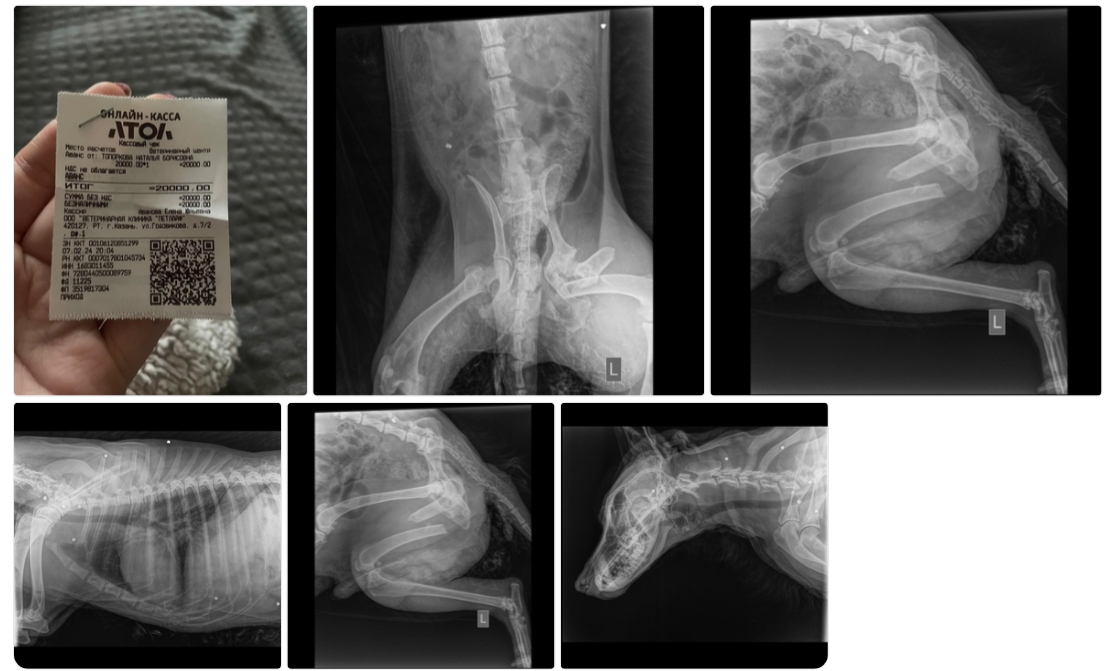

Помощь пришла, уверена он звал молча на помощь, посылая в небо мольбу избавить его от боли, адской боли , многочисленные переломы И ПУЛИ!

Да, вновь расстрелянная собака, за что?

Гигантский путь к выздоровлению, проведена пока 1 операция, через месяц вторая, Честер крупный малыш, для нас он малыш, так как беспомощный и ходить только учится. Стационар теперь его р

Первая операция, первые шаги на помочах, боль при каждом движении, так как прооперированная лапка болит от сложного перелома и вторая лапа из- за травмы и долгой неподвижности атрофировалась и опоры на нее нет.

Сумма к сбору 69 177, 40 рублей.

все чеки и фото 👇: